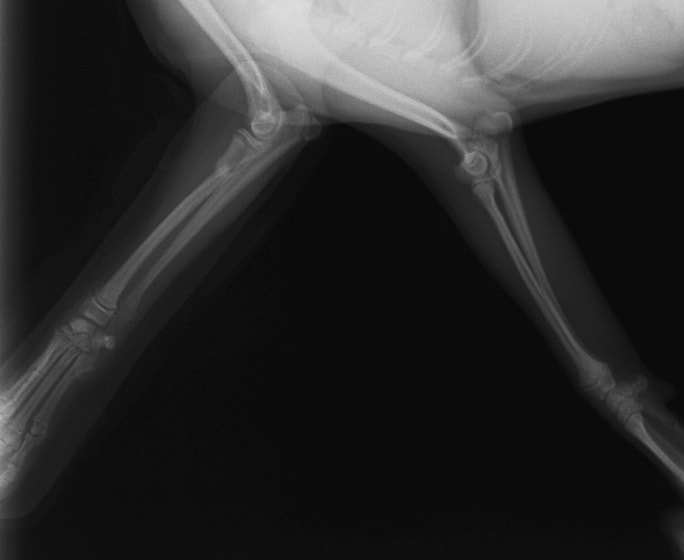

症例3:キルシュナーワイヤーのピンニングによる整復

ペルシャ猫 11ヶ月齢 雄

他院にて左大腿骨遠位の成長板骨折(salter-harrisⅠ型)が認められており、治療相談を目的として来院。当院にて、キルシュナーワイヤーを用いたピンニングにより骨折部位の整復を行いました。術後の経過は良好で、現在も経過観察中です。

術前レントゲン

術後レントゲン